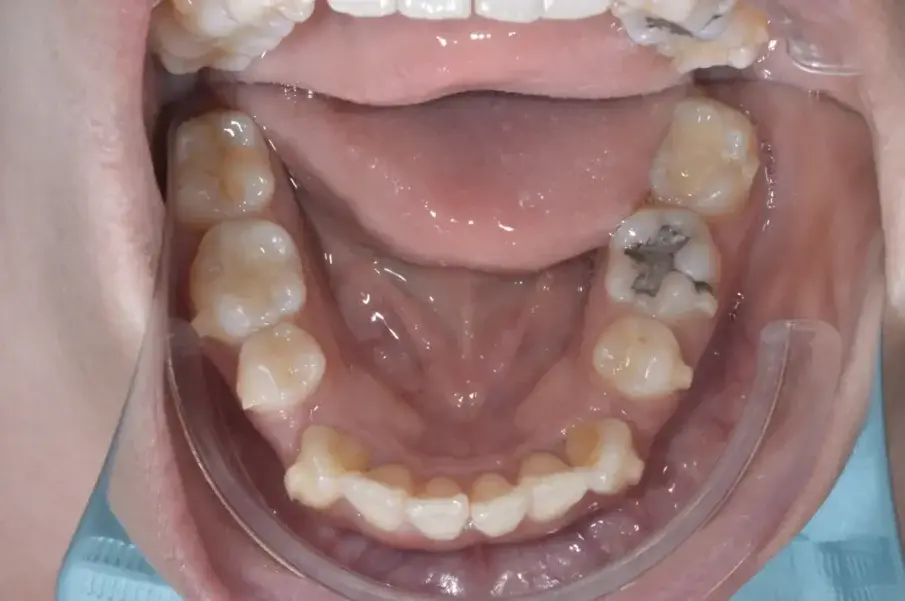

Фиг. 3а: Първоначални оклузални изображения.

Фиг. 3b: Първоначални оклузални изображения.

Фиг. 3c: Първоначални оклузални изображения.

35-годишна пациентка постъпва със струпване на зъби, болки в мускулите и ставите и главоболие след събуждане. При прегледа се установява I скелетен клас със струпване и бимаксиларна протрузия. Изследването на лицето показа конвексен профил с изпъкнали устни и квадратна форма на лицето, която се засилва при усмивка (фиг. 1-4). Тя съобщава за бруксизъм и се наблюдава двустранна хипертрофия на масетерите, но няма изменения в темпоромандибуларните стави.